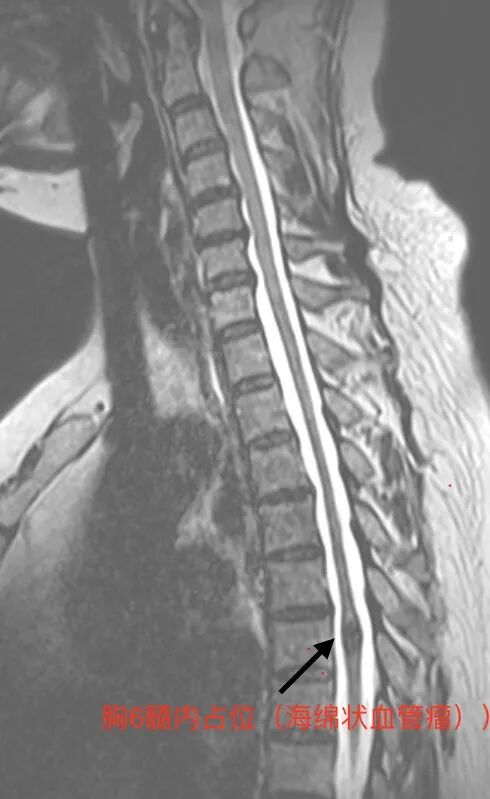

脊髓血管畸形是一种发病率不足千分之一的罕见疾病,因血管结构异常可导致脊髓受压、出血甚至永久性瘫痪。本例患者畸形血管团位置深、毗邻重要神经传导束,且异常血管错综复杂,稍有不慎即可能引发术中大出血或神经功能损伤。此类病例的诊治对医疗团队的技术水平与应急能力提出极致挑战。

术前:放射影像科通过MRI平扫及增强锁定畸形范围,神经外科、骨伤科、麻醉手术科、心内科及重症医学科多学科讨论,明确手术及围手术期风险,制定应急处理方案;